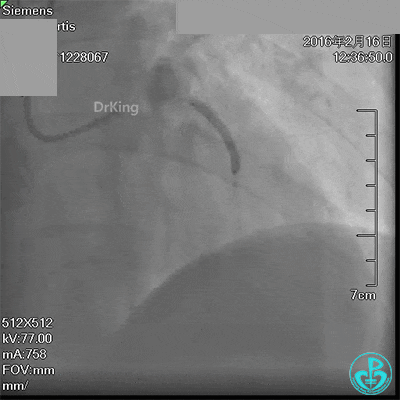

急诊冠脉造影发现粗大前降支近端严重狭窄,行PCI处理,支架膨胀良好,血流3级。

急诊术中导丝在锁骨下通过困难,曾在局部推注造影剂造影,回顾造影结果发现局部小血管破裂造影剂渗漏。